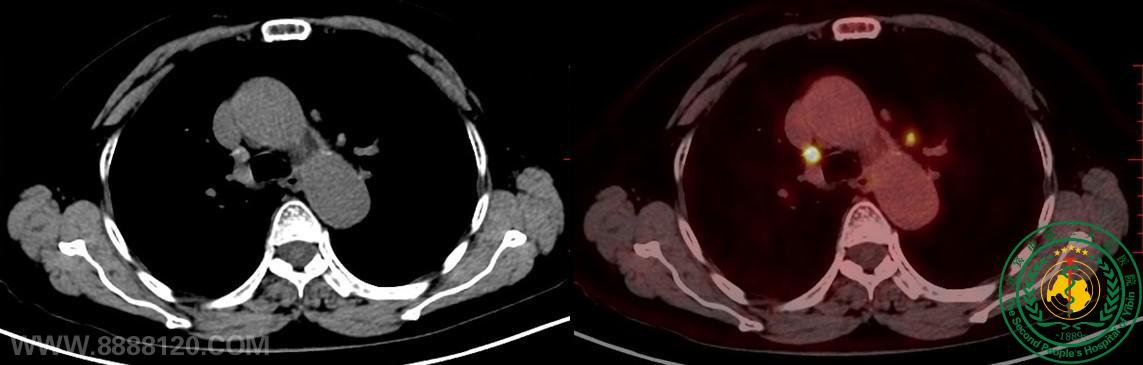

宜宾首例——华西宜宾医院核医学科顺利完成首例PET/CT检查

宜宾首例——华西宜宾医院核医学科顺利完成首例PET/CT检查52710